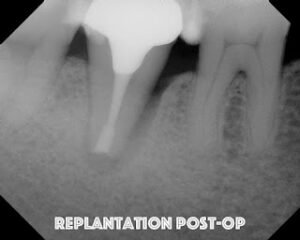

The tooth is replanted into the socket within 10 minutes of extraction. Firm pressure is placed for an extended period of time. No splinting

A seven year recall finds tooth #31 asymptomatic and fully functional. While the mesial bone looks irregular, there is no periodontal pocket. If you look at the initial photo of the extracted tooth, you can see the periodontal ligament, but there appears to be an area where the ligament had been lost. There was not visible fracture on that area of the root at that time. My assumption is that the pdl may not have ever reformed in that area – causing the current radiographic appearance.

It is interesting how a perfectly good root canal and retreatment failed to give the desired results, but a last ditch effort with replantation has been successful up to this point.